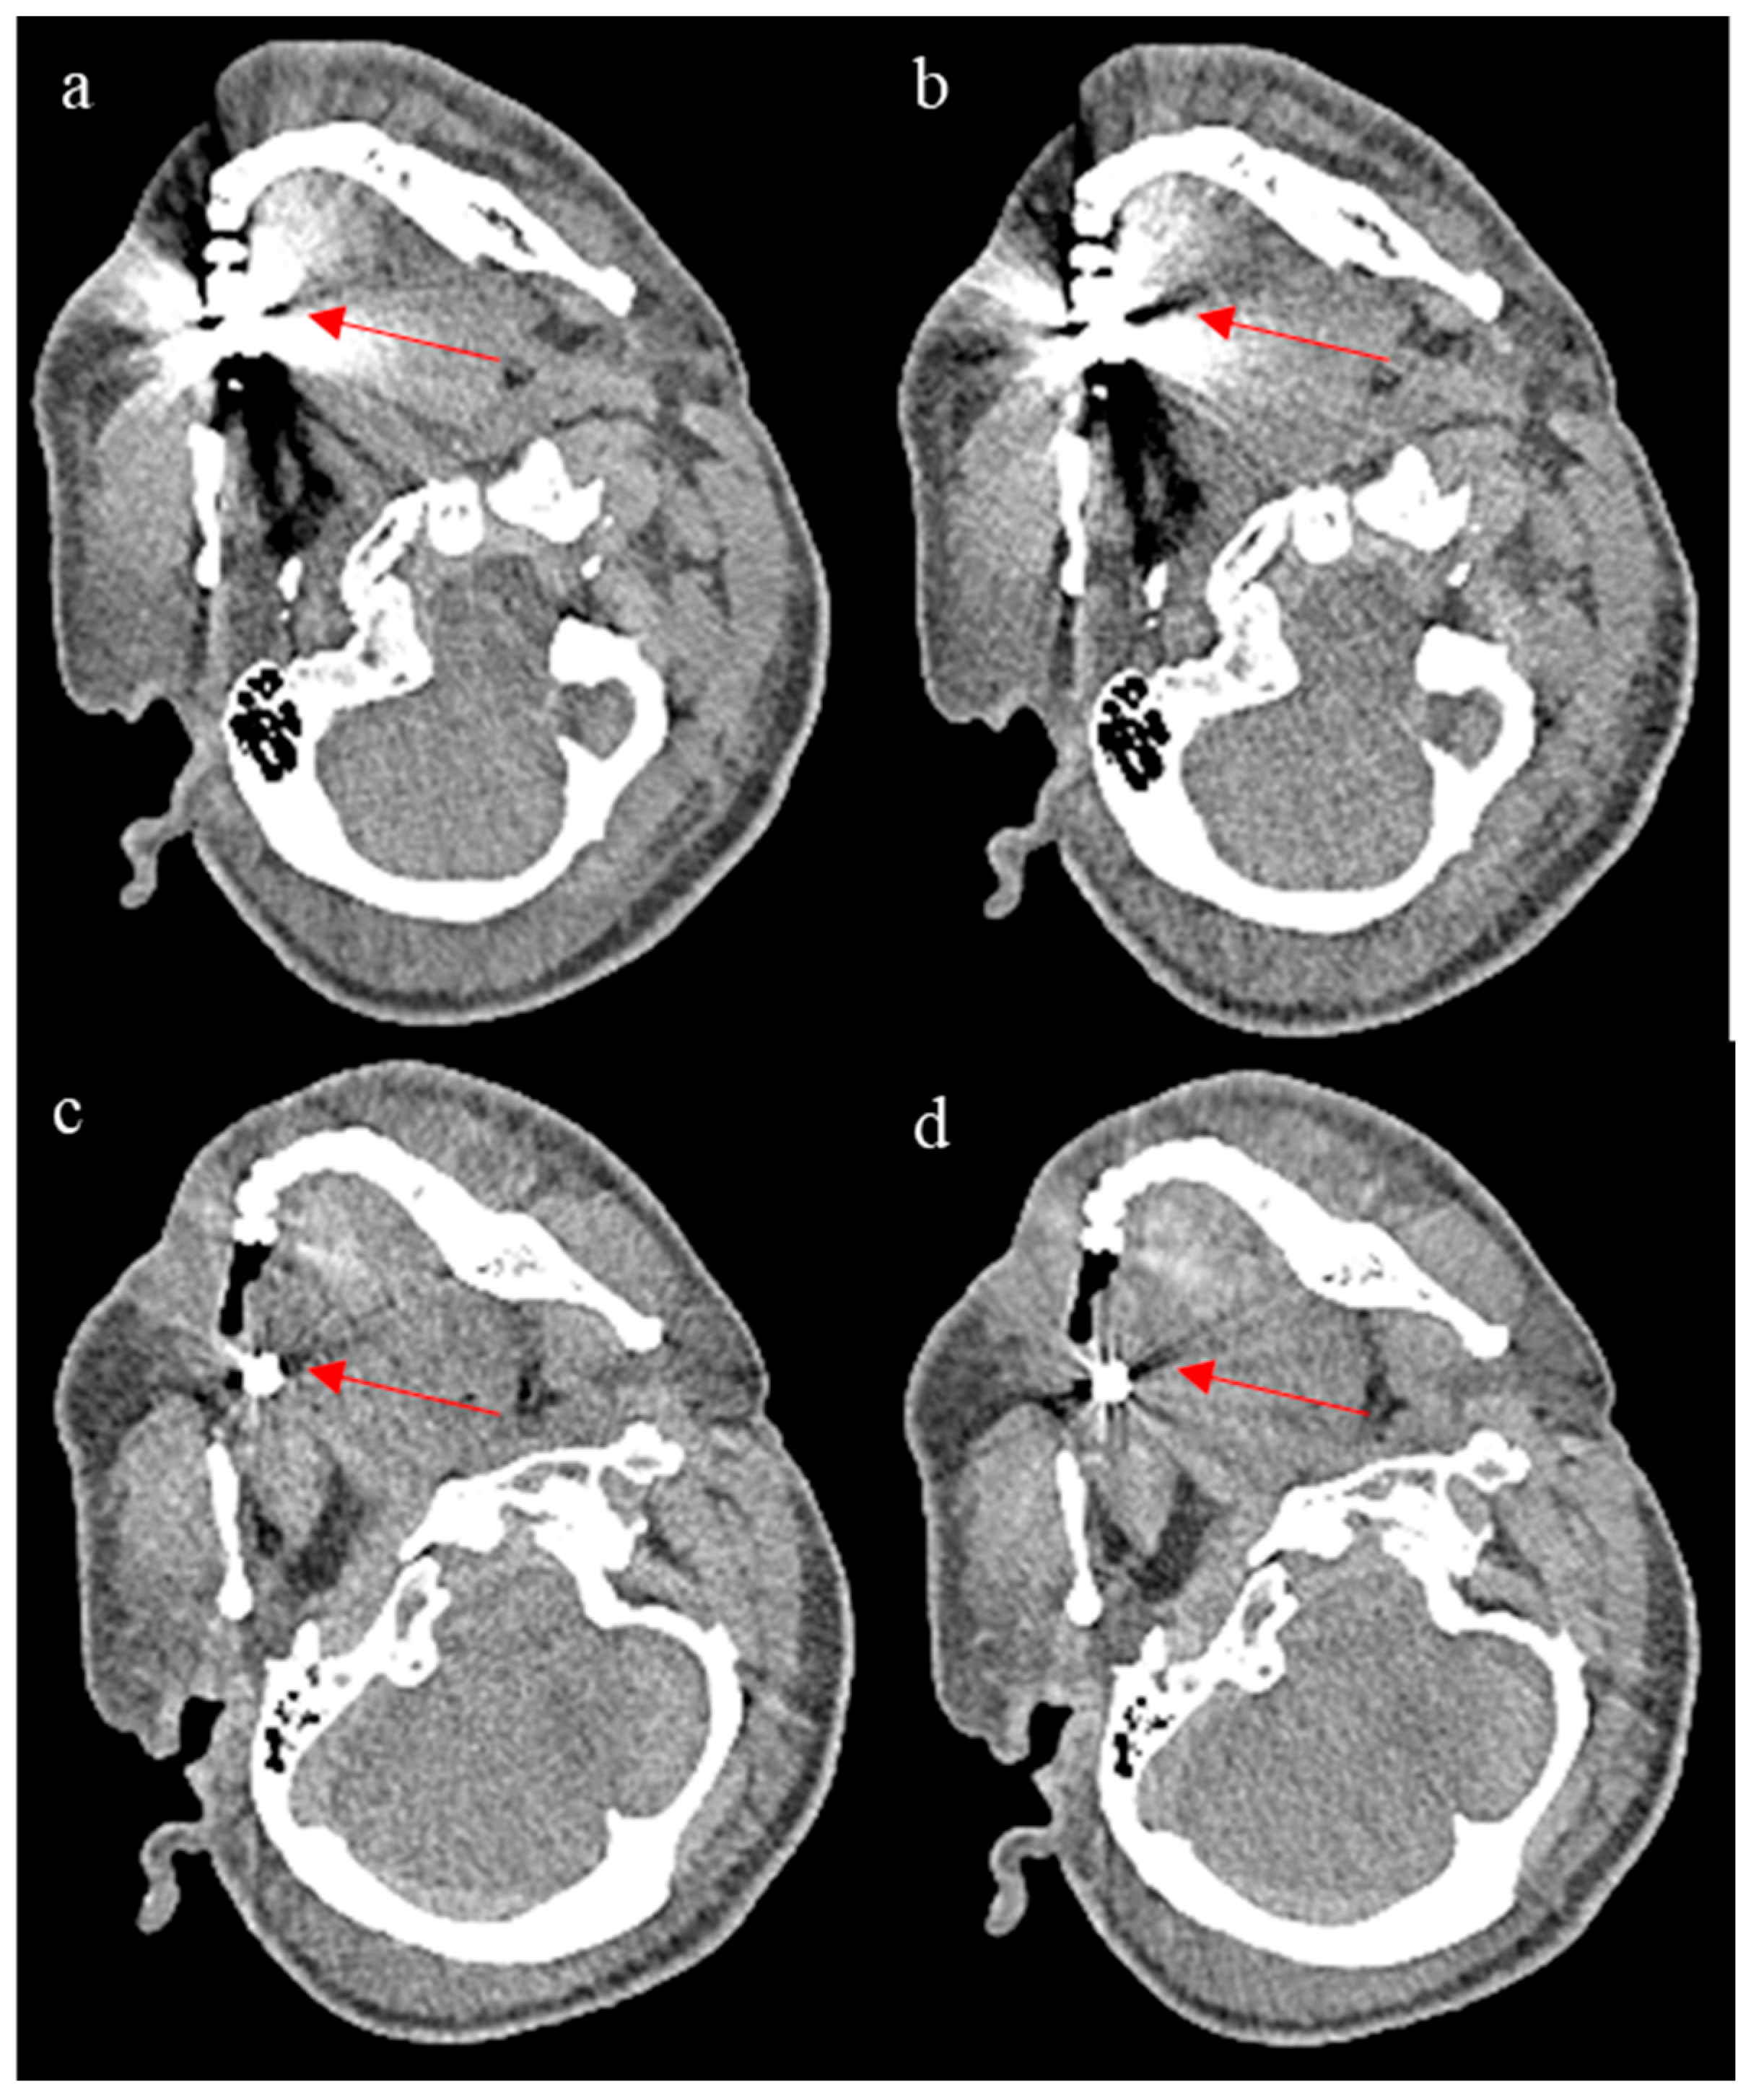

Figure 7.

The figure shows ErisNet’s performance on CT images containing metallic artefacts. (a,c) are images processed with ErisNet showing noise reduction compared to the corresponding low-dose inputs (b,d), respectively. The red arrows highlight specific regions where noise reduction in metal artefacts can be appreciated in the processed images. Although both cases (a,c) show some degree of noise reduction, as indicated by the arrows, the extent and quality of the improvement vary between the two scenarios.